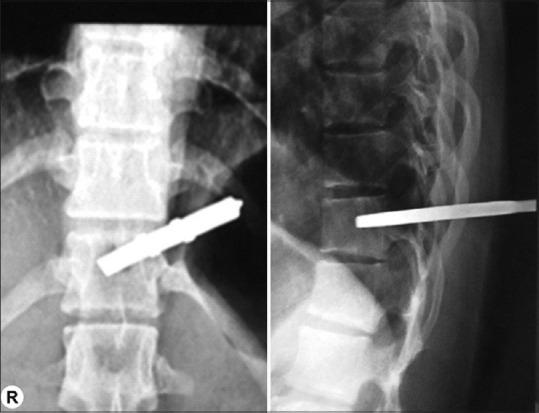

Penetrating spinal cord injury with screwdriver in situ, leading to Brown-Sequard syndrome.